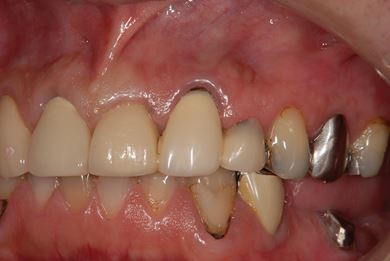

治療前

• 治療前